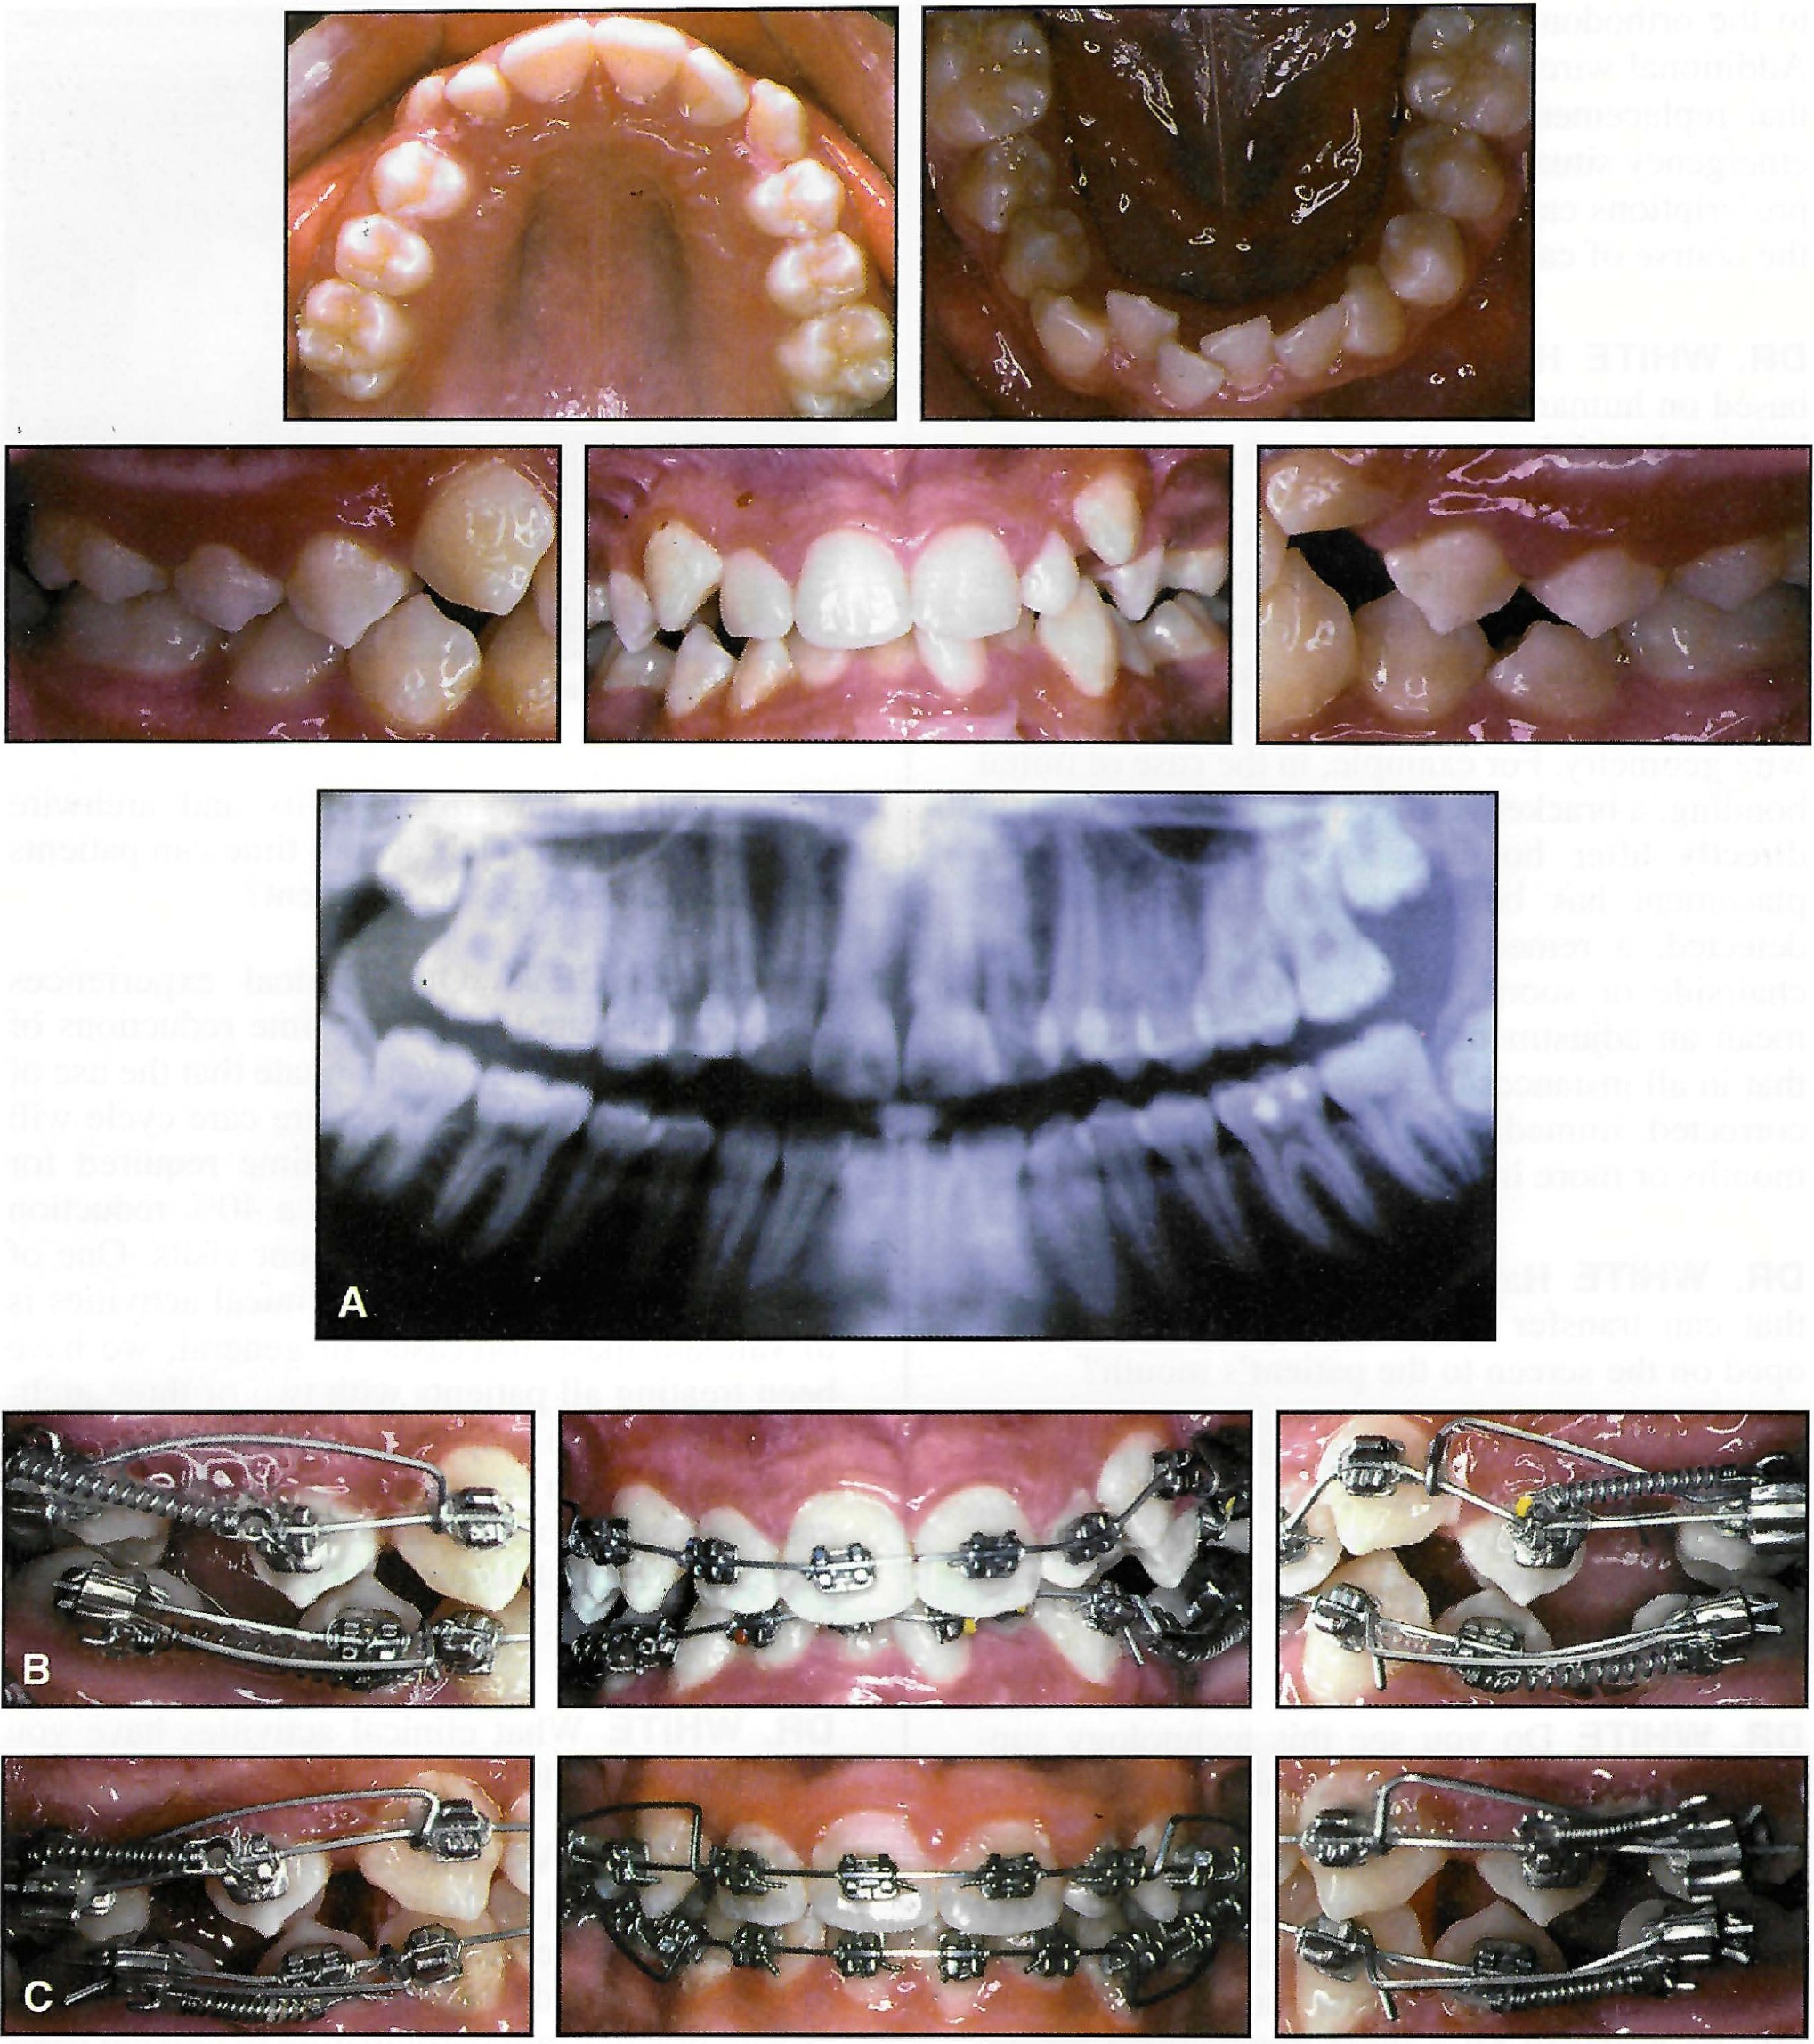

DR. SACHDEVA Our clinical experiences have demonstrated treatment time reductions of 50% during finishing. We estimate that the use of this system throughout the entire care cycle will save more than 30% of the time required for overall treatment, and provide a 40% reduction in the number of required patient visits. One of the objectives of our current clinical activities is to validate these forecasts. In general, we have been treating all patients with two or three archwires. We have experienced these efficiency gains with both extraction and nonextraction cases. Most important, these improvements have been realized with improvements in overall quality of finish (Fig. 6A and 6B).

Fig. 6 A. Patient before treatment. B. After extraction of four second bicuspids and placement of initial appliances. C. After four months of leveling, alignment, and space closure with .017" × .025" TMA tipback springs and .017" × .025" Copper Ni-Ti** 35°C wires (continued in next page).

Fig. 6 (cont.) D. After six months of treatment. Note translation of canines and premolars during space closure. E. After 10 months of treatment, placement of .019" × .025" TMA finishing wires. F. Removal of appliances after 12 months of treatment.